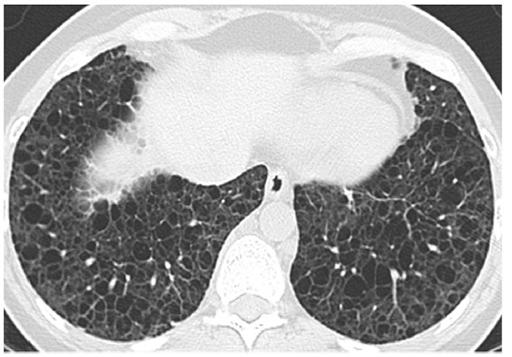

Vital signs and cardiopulmonary exam were normal. Basic labs and EKG were also normal. Due to an elevated D-dimer of 570 ng/mL, she had a CTA chest done.

CXR and CT Chest

What is the most likely etiology of her diffuse cystic lung disease?